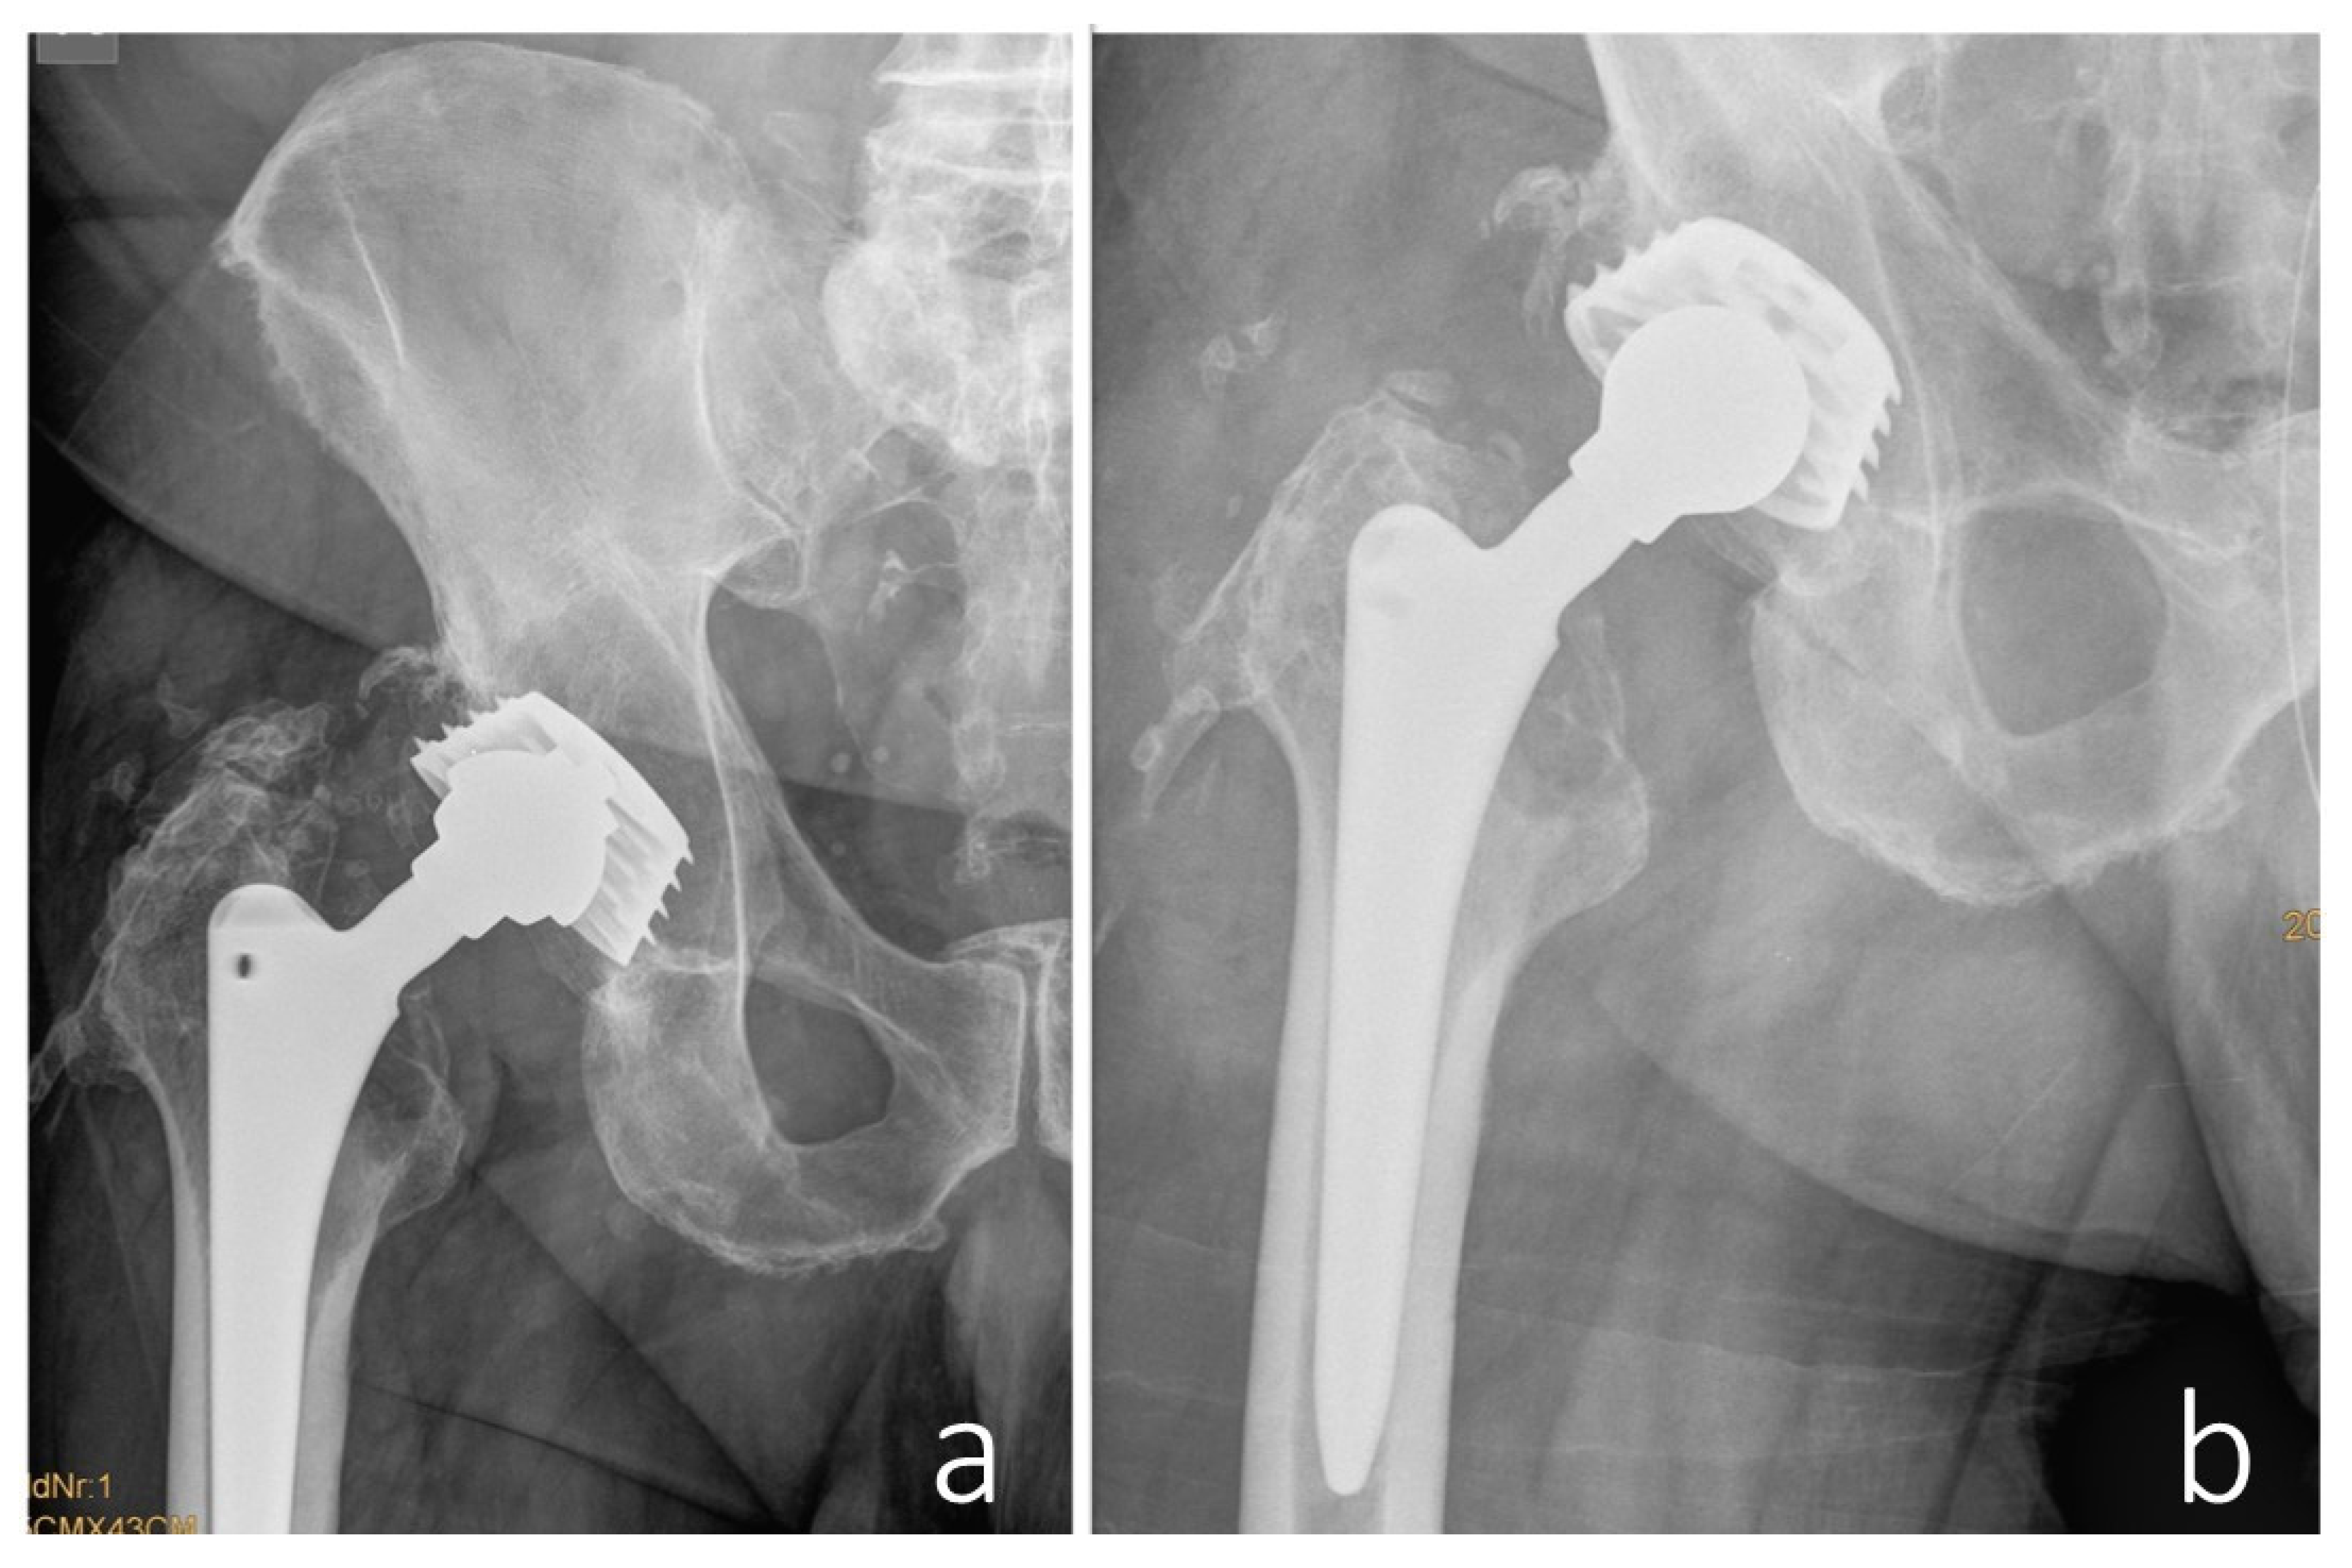

Postoperatively, there was notable improvement in lower extremity swelling, attributed to decompression of the neurovascular bundle. However, further diagnostic workup revealed a bacterial infection caused by methicillin-resistant Staphylococcus aureus (MRSA), confirmed through implant sonication, tissue cultures, and PCR analysis. Targeted antibiotic therapy was initiated according to the antibiogram, but the infection persisted despite appropriate treatment. As a result, a two-stage revision procedure was performed. This included thorough resection of residual pseudotumor tissue surrounding the neurovascular bundle and placement of a temporary, non-articulating, antibiotic-loaded cement spacer. Reimplantation was postponed for six months due to additional complications, including a nosocomial pulmonary infection and urinary tract infection caused by E. coli and Pseudomonas. Once these infections were resolved, reimplantation was successfully performed using a Lima Delta Multihole TT acetabular component, secured with bone screws, an angled spacer, a protrusively designed liner, a 36 mm XL ceramic femoral head, and an SL-Plus MIA high-offset femoral stem (Smith & Nephew). Unfortunately, reinfection with Enterobacter cloacae complex occurred post-reimplantation, ultimately necessitating joint resection (Figure 7).

Figure 7. (a) The status post explantation of the prosthetic components with a non-articulating cement spacer in place. (b) The situation following delayed reimplantation of the total hip arthroplasty. Due to recurrent infection, a second explantation of the hip prosthesis was required, as shown in (c).